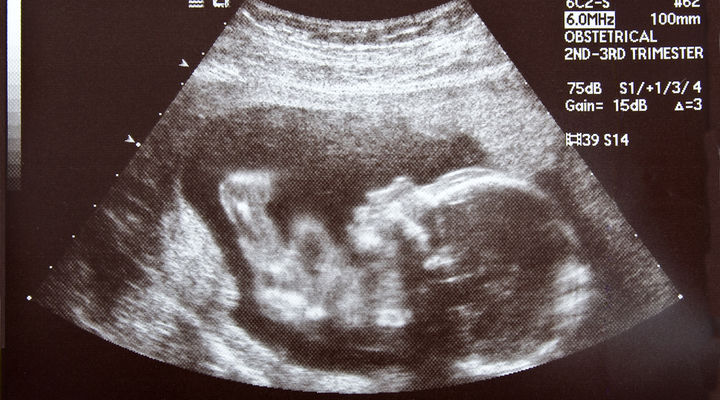

Körpənin içində qan axdığını hiss edən hər bir qadın və ultrasəs ekranında kiçik ürəyini döyəcləyən hər bir kişi bilir ki, abort həyata son qoymaq deməkdir.